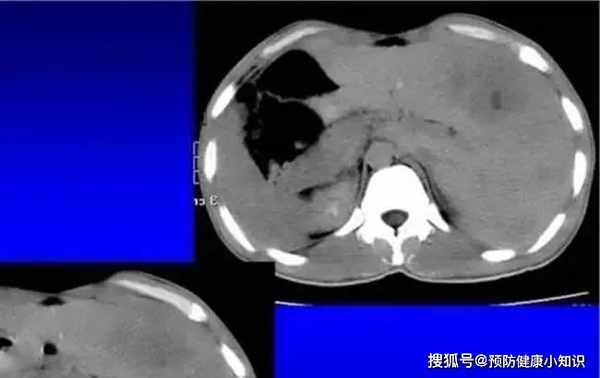

最近原本很是富態的張大姐,突然暴瘦,整個人瘦的有些脫相了,並且總是噁心嘔吐,小兒子帶她去醫院檢查,卻不料最終確診了肝癌,已經到了晚期…..